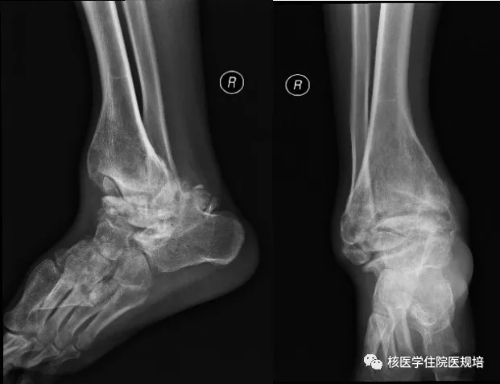

患者男性,30岁, 3个月前无明显诱因突发大小便失禁,同时伴下肢活动障碍,为进一步诊治就诊于我院。既往史:出生后诊断为先天性无痛无汗症,其他无特殊病史。查体:患者轮椅进入病房,神志清楚,对答切题;全身皮肤干燥、见多处瘢痕,皮肤痛觉缺失,指甲发育不良,脊柱生理屈度存在,无明显棘突压痛。双上肢未见明显畸形,肌力、肌张力未见明显异常。左下肢可见膝关节不规则隆起,表面不光滑,质硬,无波动感,关节屈伸正常,局部皮温正常,无皮肤红肿、破溃或静脉怒张,压痛(-);右下肢未见明显异常。双下肢感觉较弱,巴氏征(-)。实验室检查无明显异常发现。腰椎X光片及CT(图1.2)检查发现腰椎退行性变,L3、L4椎体融合,骨小梁结构模糊,L5/S1椎间盘膨出,前纵韧带钙化;多关节部位X光片示右髋关节(图3)髋臼扩大、骨质吸收,股骨头脱位,骨骺未融合,残端如刀削状,关节肿胀,内见多发碎骨片;左膝关节(图4)正常关节结构消失,关节对位差,骨端膨大,周围见多发游离骨块,股骨下段、胫骨平台见骨质破坏,关节周围软组织肿胀;右踝关节(图5)诸骨在位,胫腓骨远端膨大变形,距骨变扁,诸骨骨质密度弥漫减低,骨小梁稀疏,内外踝边缘可见骨质增生;关节间隙狭窄。为进一步了解全身骨病变情况行99mTc-MDP全身骨显像(图6)。

图5.